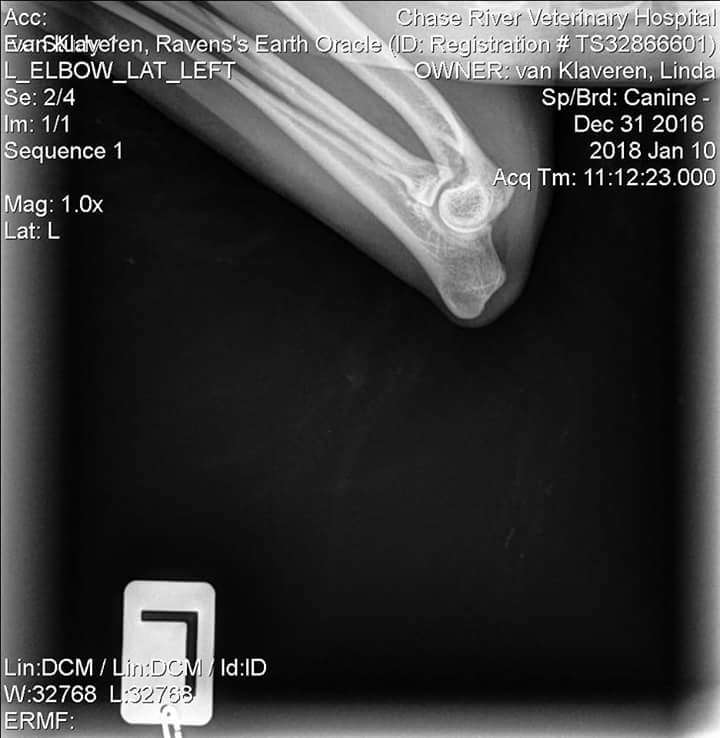

OFA Test Results:

Test Date - Jan. 10, 2018

Report Date - Jan. 15, 2018

· ELBOW PRELIMINARY NORMAL